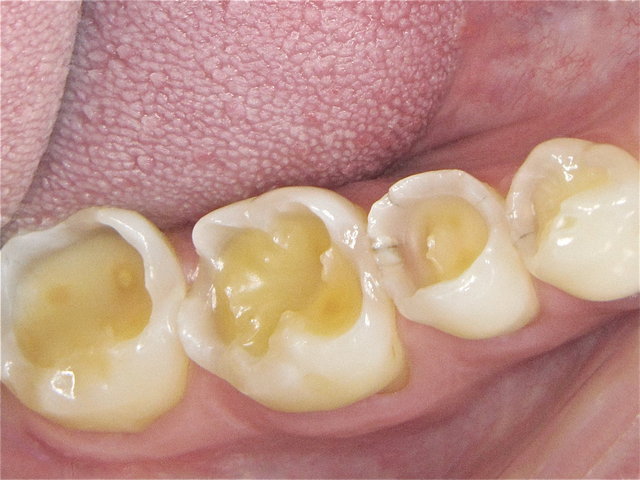

Säuregeschädigte Zähne ...

Composit-Füllungen by CLINICDENT ✓